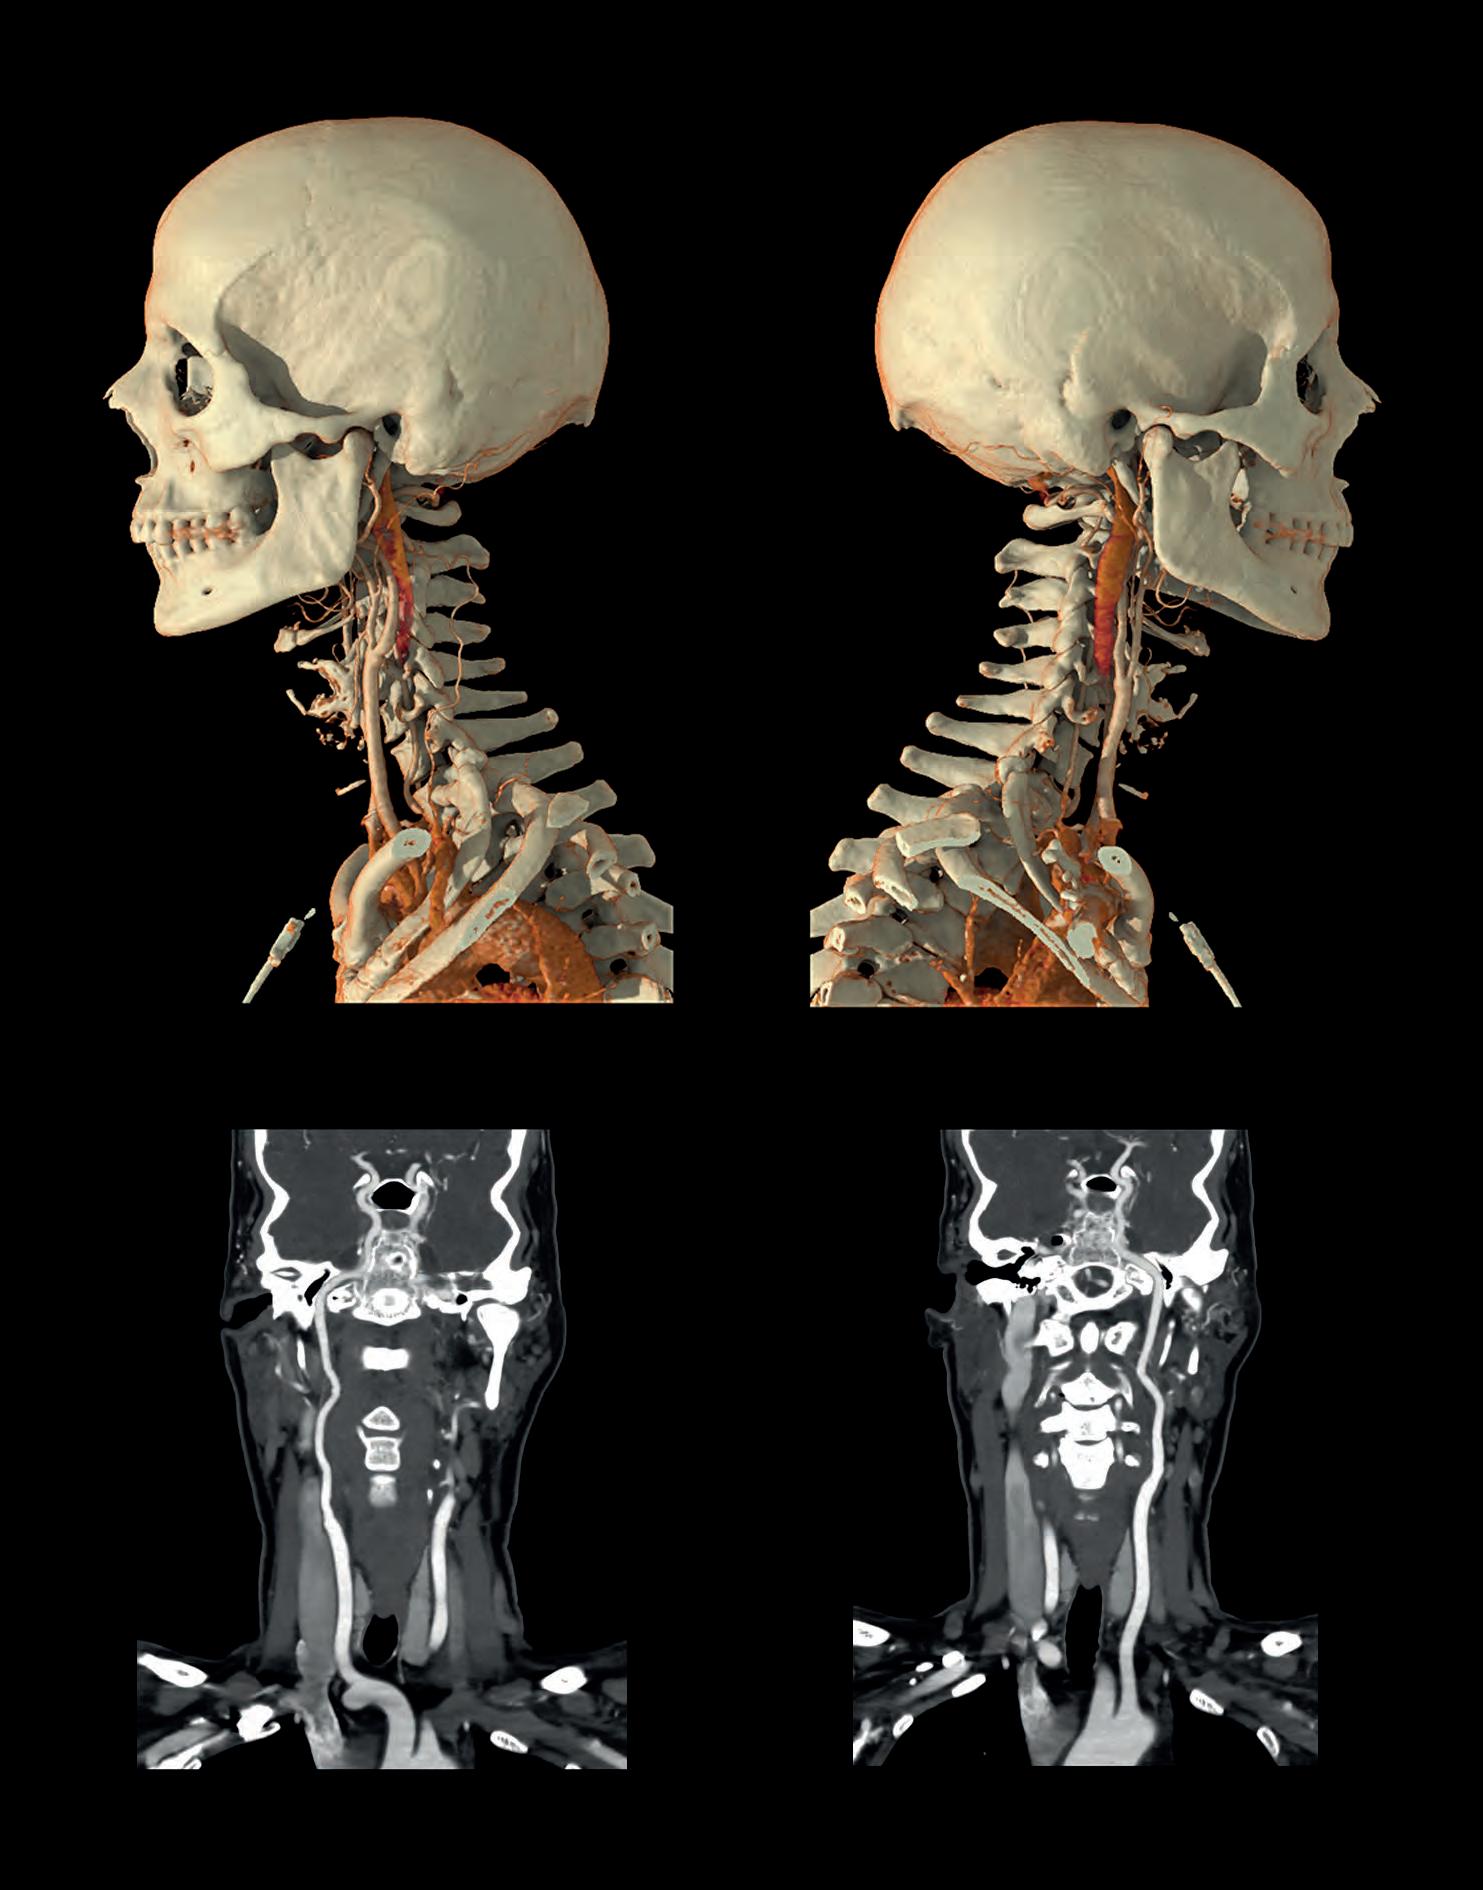

Fig

1. Carotid Angiography using AI-assisted CT: Low-dose Ultra Helical CT Angiogram of the Carotids and Circle of Willis for stroke work-up.

AI-assisted

CT provides clear visualisation of contrast enhanced vessels and surrounding soft tissue for fast and confident rule-out of occlusion.